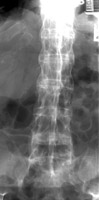

Diagnosis:Ankylosing Spondylitis Discussion:Anterior and lateral radiograph of the lumbar spine which reveals near complete fusion of all of the vertebral bodies. Spinal changes which include squaring of the vertebral bodies and fusion between adjacent levels. The fusion is secondary to syndesmophytes and resembles a bamboo stalk. This is most commonly found in ankylosing spondylitis. References: